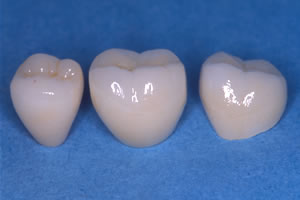

![]() セラミック冠